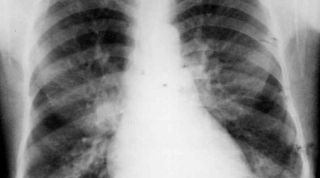

Ir al médico y salir con un diagnóstico que solo genera más dudas, es algo frustrante para muchos pacientes. Por eso, buscamos de explicarles, de la forma más sencilla, diferentes tipos de lesiones y sus cuidados